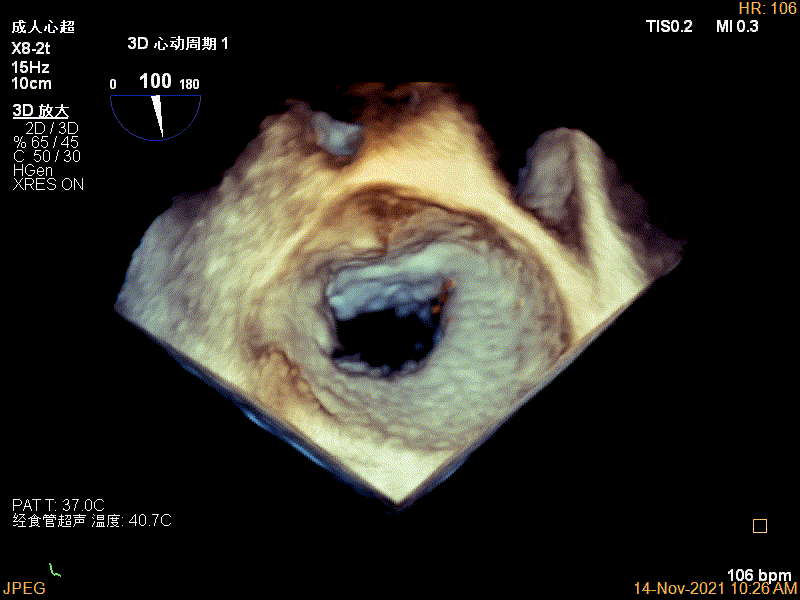

Qlab软件勾画估测瓣口面积约:6.52cm²

3D视图下进夹子并建立trajectory

3D视图打开夹子

3D视图两个夹子近似并排排列